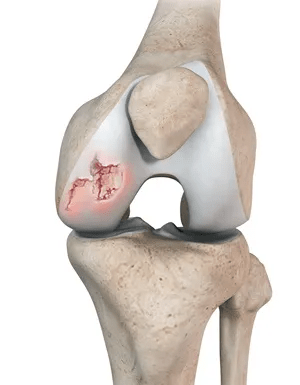

But why does this happen? Cartilage wear and inflammation play key roles, leading to that nagging ache.

One study found decreased cartilage deterioration signs with lauric acid. But wait, the next benefit dives deeper into pain relief.

Benefit 7: Supporting Cartilage Health

Picture Emily, 48, a hiker whose trails became shorter due to knee wear. She feared giving up her passion.

Studies on virgin coconut oil with vitamin D suggest reduced cartilage degeneration. Emily tried it in smoothies.

Her steps felt lighter. Research highlights potential protective effects on joint structures.

Research combining coconut oil with nutrients suggests delayed osteoarthritis progression. Patricia’s story mirrors this.